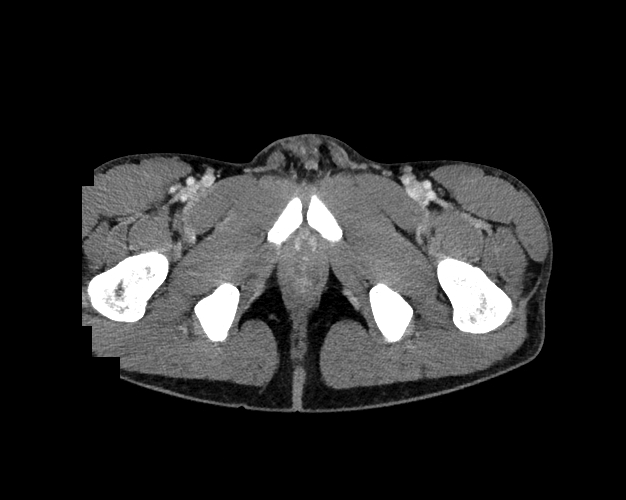

Pelvis

Covers pelvic MRI anatomy.